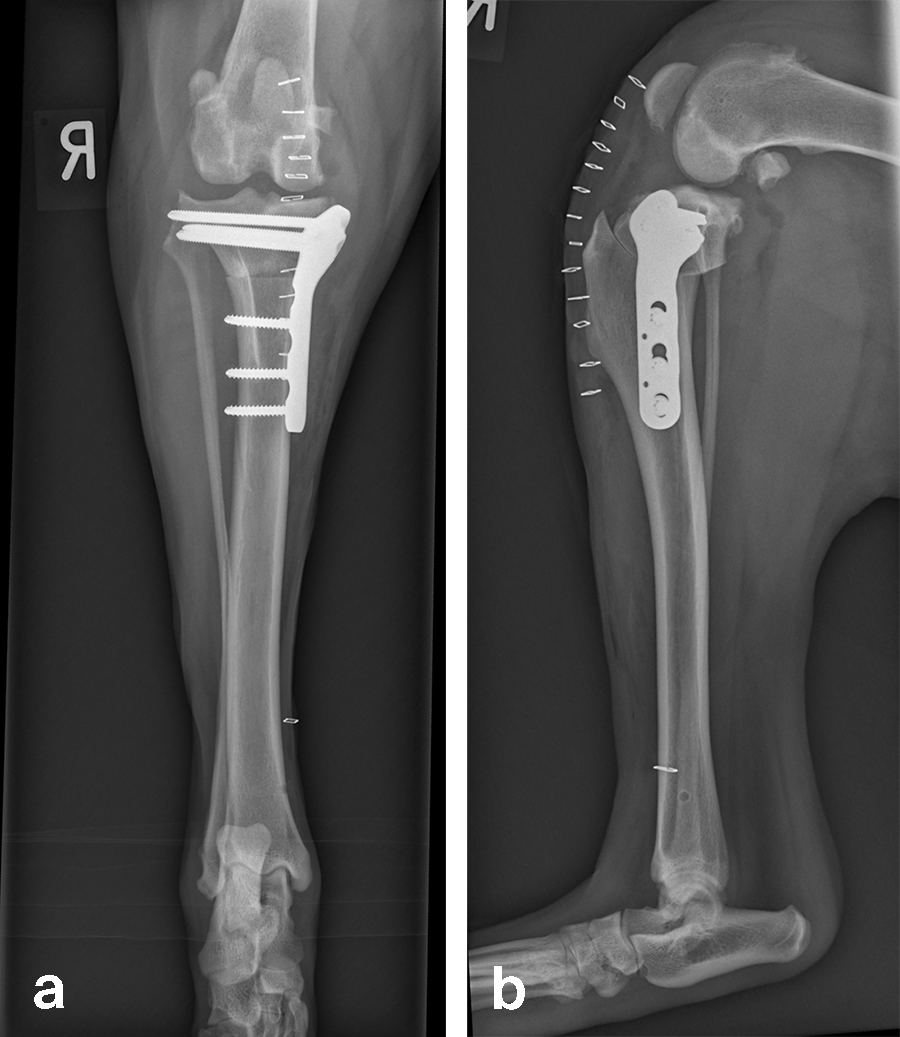

Based on preoperative templating, a 21 mm radial saw blade was used to perform an osteotomy of the proximal tibia. The plateau was leveled to a final target slope of 5° and the osteotomy was stabilized with a 3.5 mm ARC TPLO plate.

In Rosie’s case, the plate fit was excellent and the TPLO was performed without complication. Postoperative radiographs illustrate excellent plate position and screw placement and compression across all aspects of the osteotomy. Rosie recovered uneventfully from surgery and at the time of recheck (7 weeks postoperation) was using the operated limb without visible lameness. The knee examination was unremarkable, and radiographs demonstrated robust healing of the TPLO.